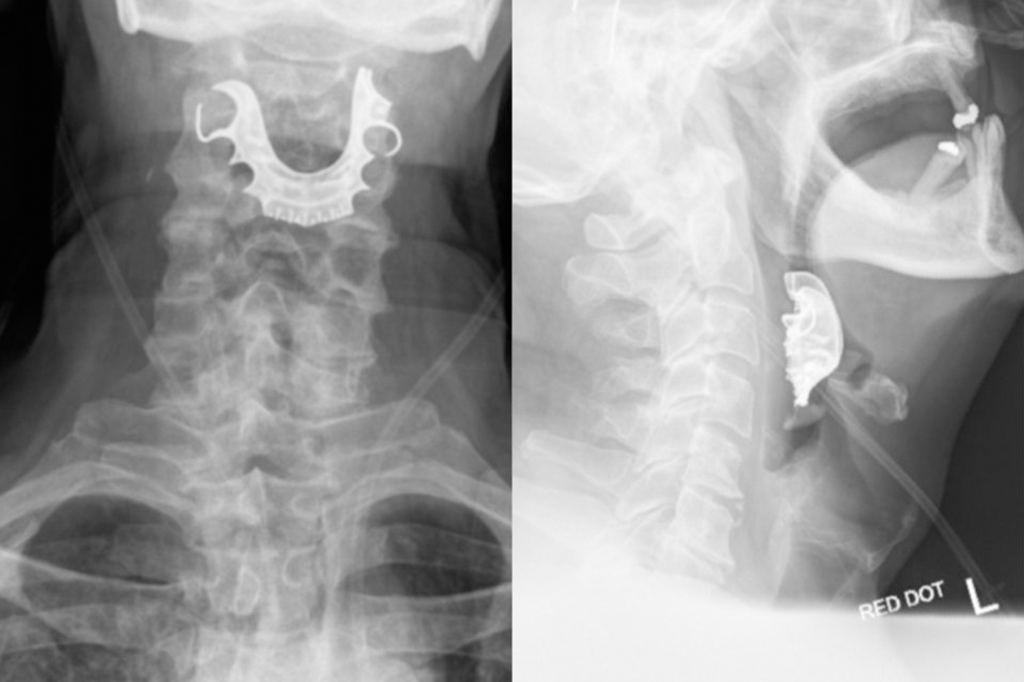

Idoso engoliu sua dentadura durante cirurgia – e ela entalou na garganta

Por Ingrid Luisa 16 ago 2019, 18h36 • Atualizado em 16 ago 2019, 19h05